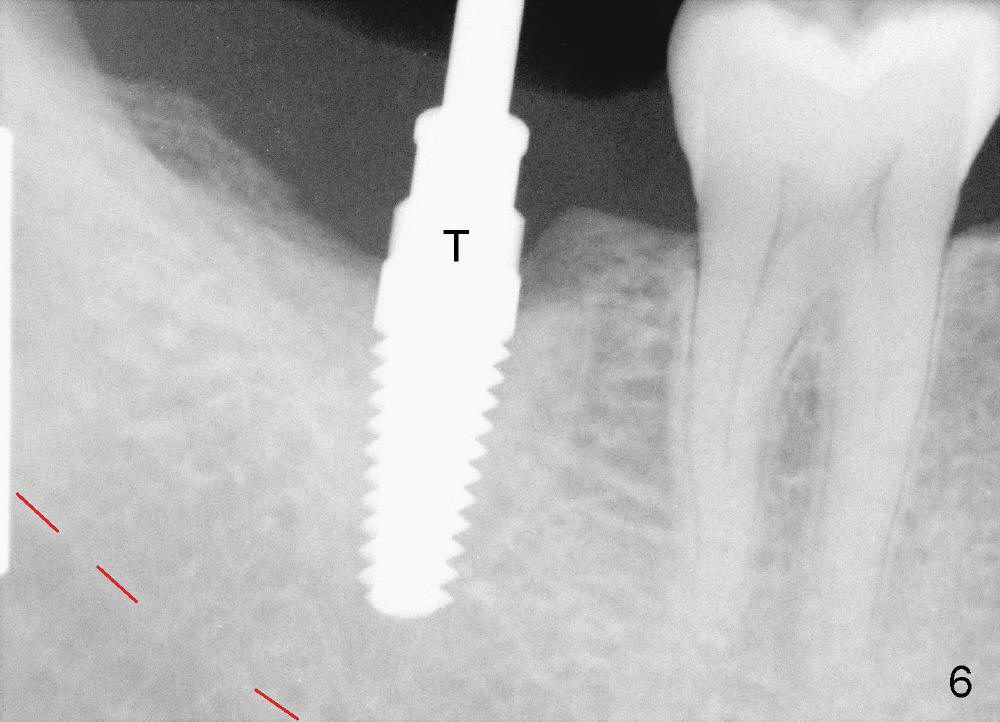

Infiltration anesthesia is administered with 68 mg of Septocaine, 34 mg of Lidocaine, 34 mcg of Epinephrine around the site of the lower right 2nd molar. An incision is made. A 2 mm pilot drill is used to initiate osteotomy at the depth of 8 mm. A parallel pin is inserted for the 1st intraop PA (Fig.4: P), which shows once more time the likelihood of incooperation from the patient. Combined with the information from CT, it appears alright to continue increasing osteotomy in the diameter and depth until 5x11 mm (Fig.5,6 (T: tap)). A 6x14 mm tap is inserted at 11 mm in bone. When the tap is removed, an explorer is used to check the intrigity of the osteotomy walls. No vibration is palpated linguoapically during drilling and inserting taps. There is no abnormal hemorrhage from the osteotomy. Finally 6x14 mm implant is placed as expected (Fig.7). The wound is healing 6 days postop (Fig.8).